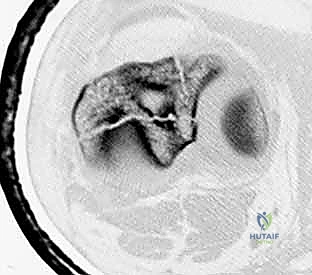

يبدأ التشخيص بالفحص السريري الدقيق لتقييم حالة الجلد، النبض، والأعصاب. يتبع ذلك إجراء الأشعة السينية (X-rays) من زوايا متعددة لتحديد موقع وشكل الكسر بدقة. في حالات الكسور المعقدة أو التي تمتد إلى مفصل الركبة أو الكاحل، يطلب البروفيسور هطيف إجراء أشعة مقطعية (CT Scan) للحصول على صورة ثلاثية الأبعاد تساعد في التخطيط الجراحي الدقيق.

باستخدام جهاز الأشعة السينية المتحرك داخل غرفة العمليات (C-arm Fluoroscopy)، يتم سحب الساق وإعادتها لوضعها التشريحي الصحيح (Reduction) دون فتح منطقة الكسر.